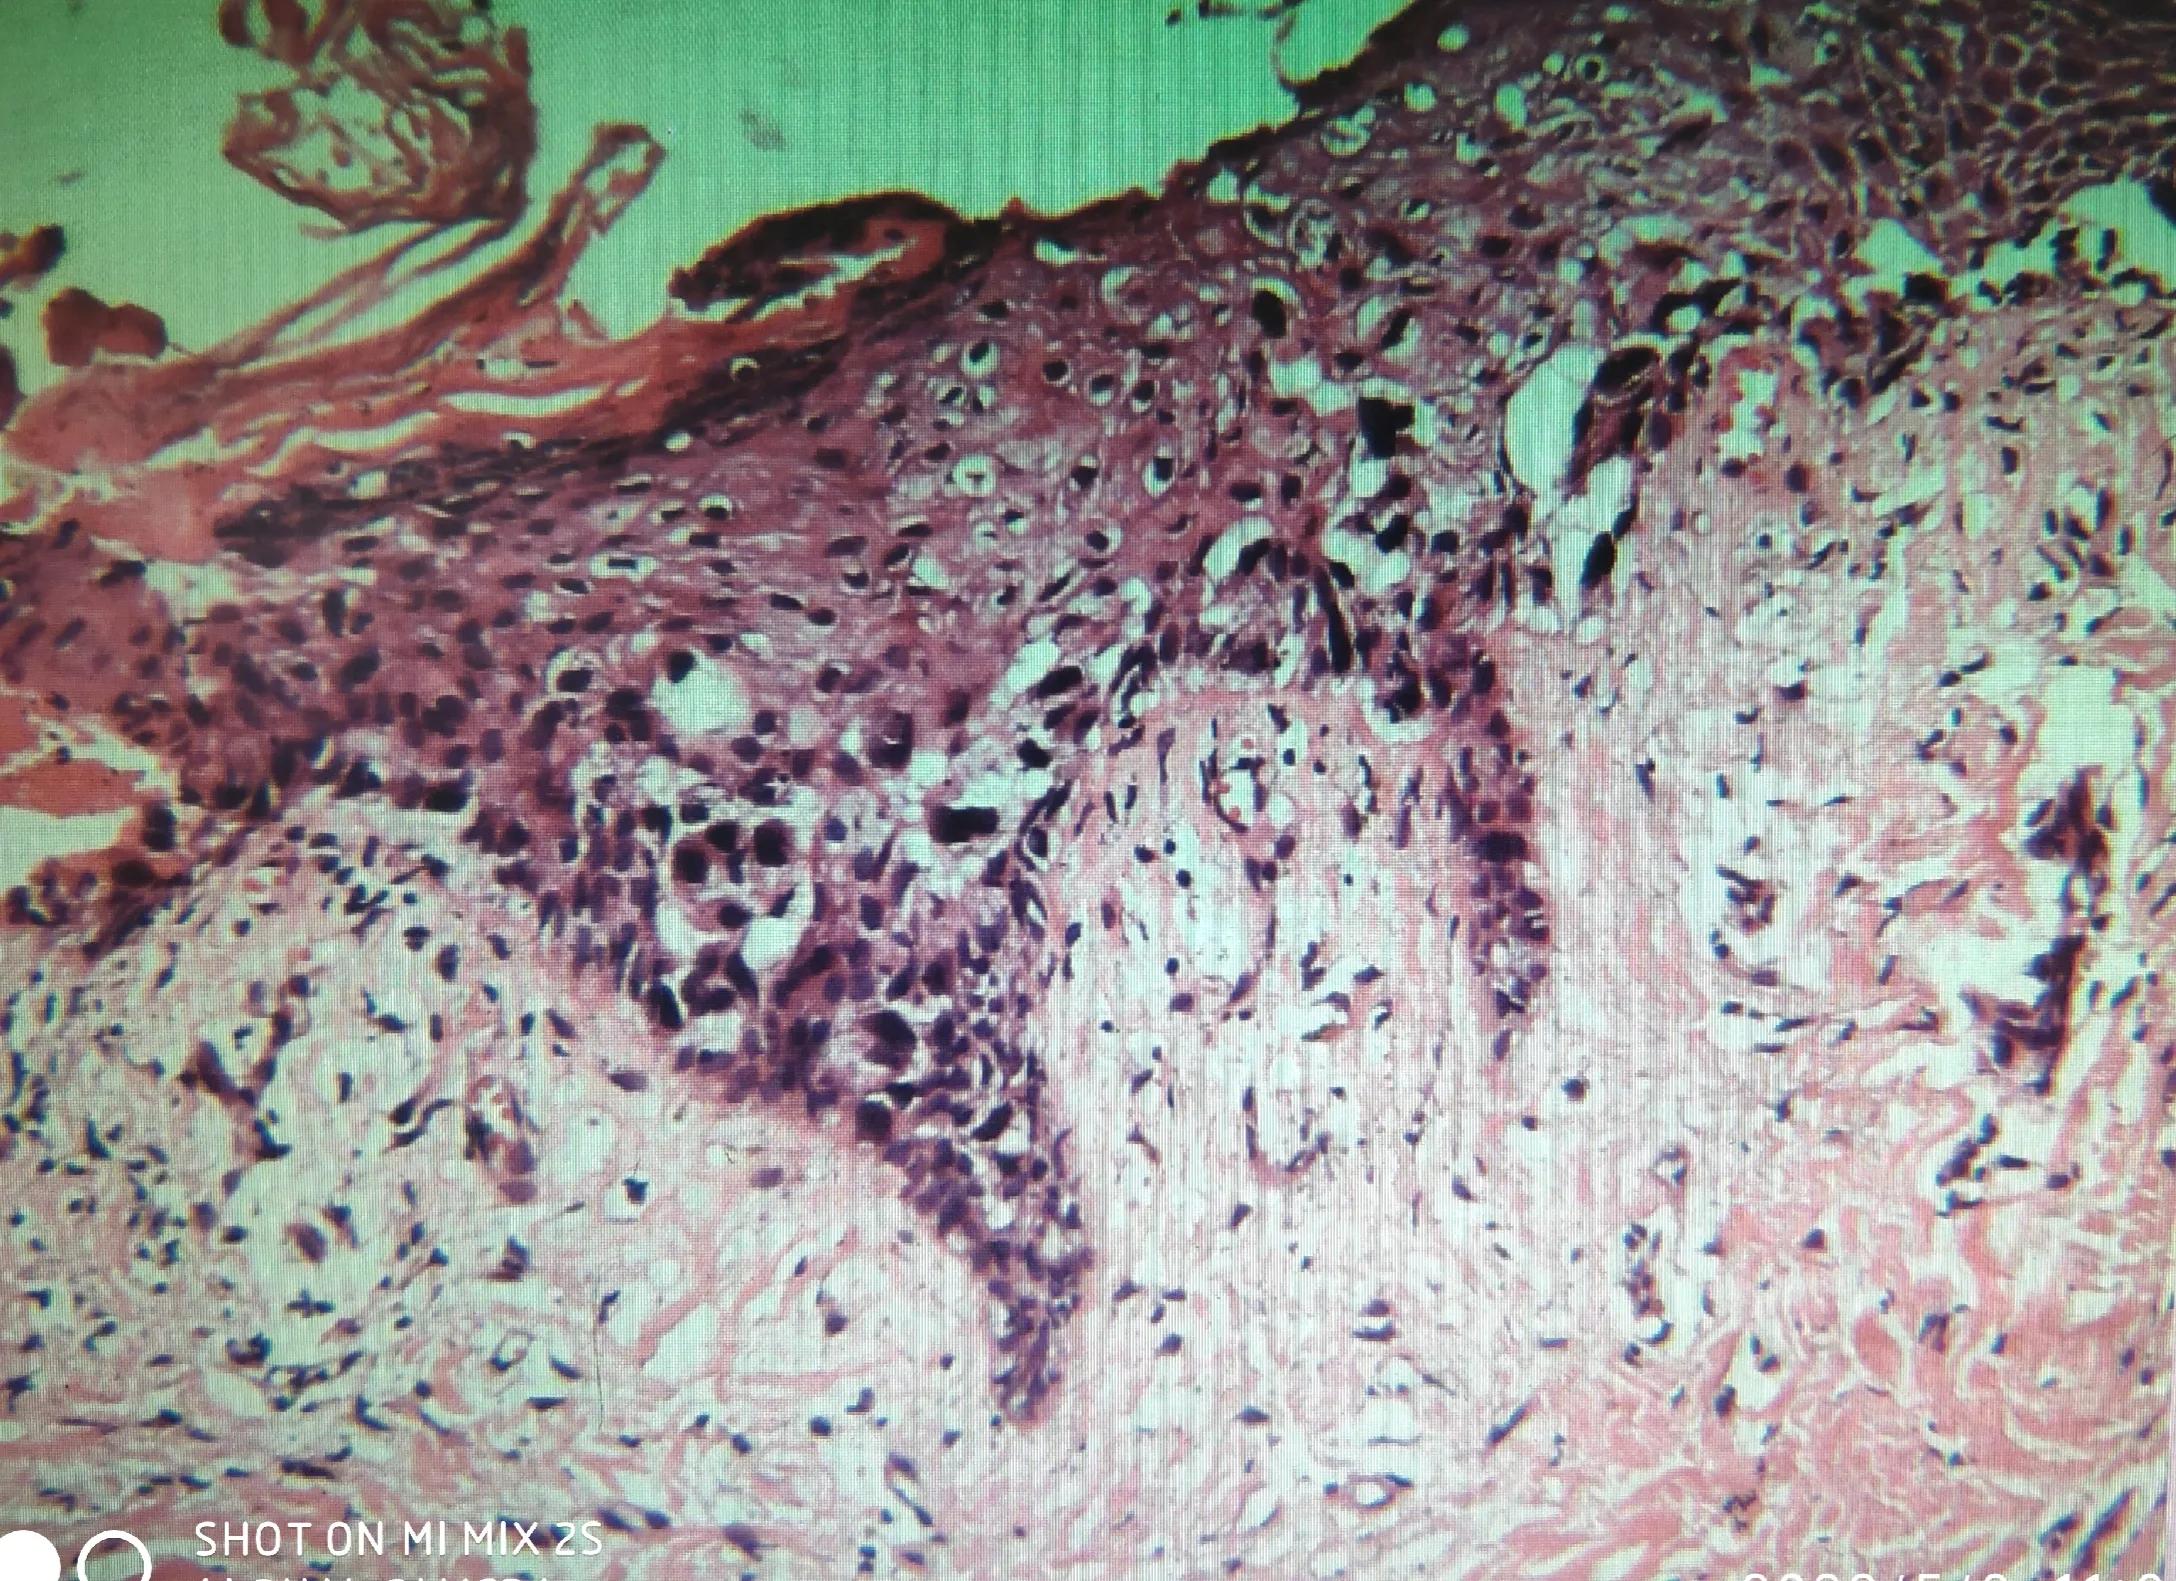

镜下见小块皮肤组织,表皮中基底及棘层见数个空泡状的异形细胞,胞核大而深染,异型性大,高度怀疑是湿疹样癌(paget病)。

乳晕活检的切片镜下观,100倍

乳头与乳晕交界处100倍

表皮基底及棘层见Paget细胞

肿瘤细胞胞质透亮,细胞核大,核仁明显,单个或数个成巢,散在分布于表皮的生发层和基底层,部分区域表皮萎缩、缺失、糜烂,上皮下间质见较多的炎症细胞浸润。乳头间质中个别末端输乳管上皮内有空泡样的瘤细胞,